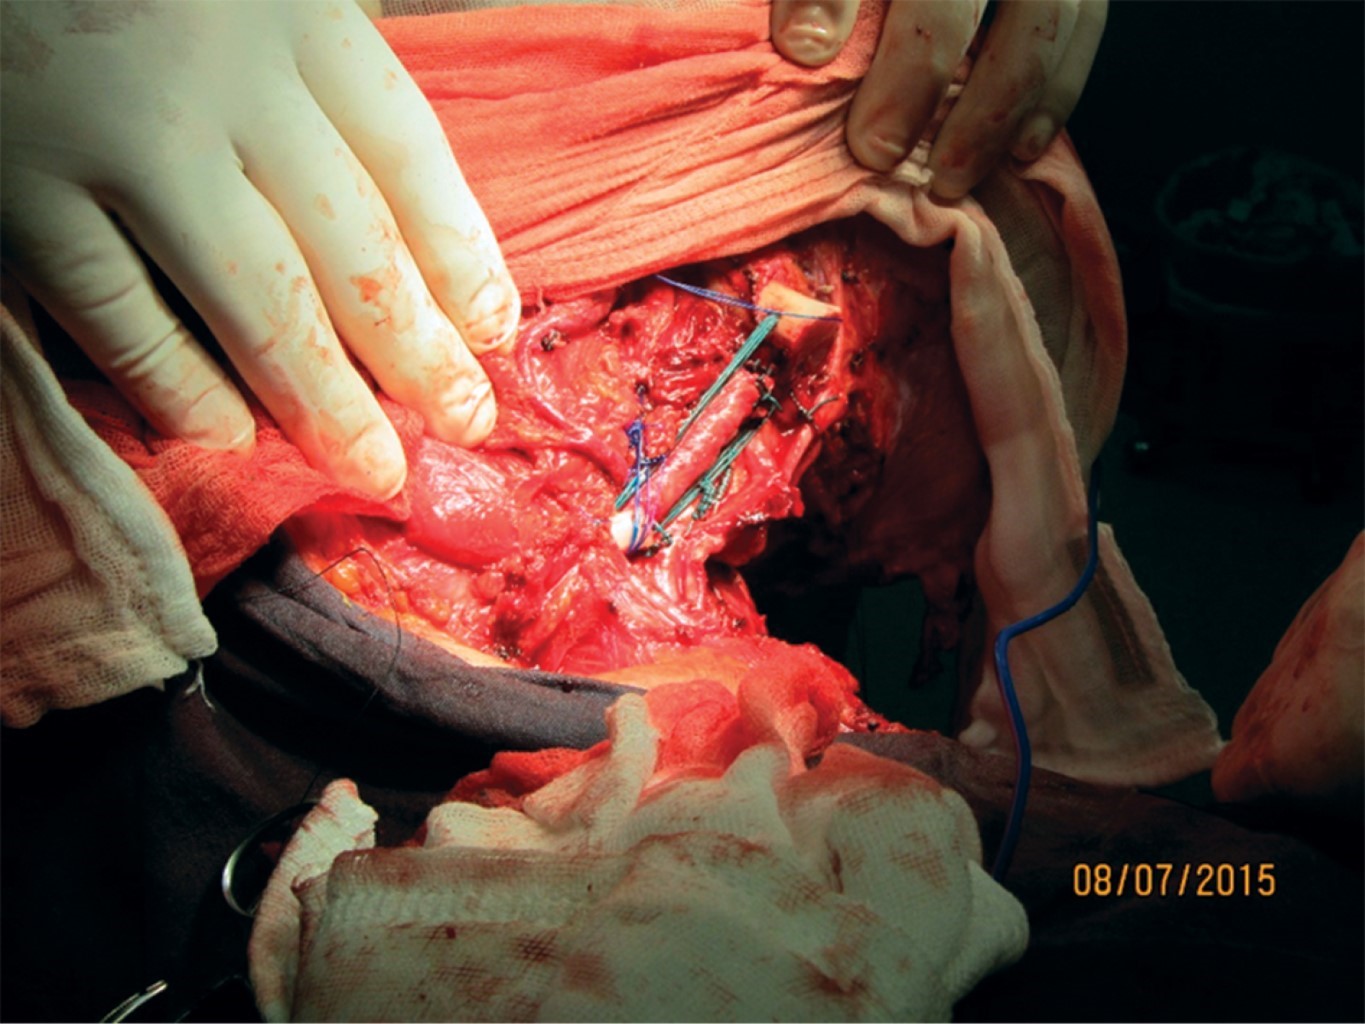

On July 2015, a Tikhoff-Linberg type 4 right shoulder girdle resection surgery was performed without the use of a scapula or humerus prosthesis. Cephalothin was administered as a preoperative antibiotic without any additional drug. The surgical approach was through an incision and lifting of a supraclavicular skin flap, with dissection of the deltoid and suprascapular muscles. Once the area was exposed (Figure 3) the dissection of the mass was performed with resection of the clavicle two distal thirds, as well as the elimination of the proximal humerus up to its surgical neck. The humerus was anchored to the clavicle with a polyester suture #3. The aponeurotic fasciae were closed in planes with a 2-0 vicryl anchored continuous suture. In the postoperative period, there was no dehiscence, seroma, or hematoma formation, nor infection.

The approximate incidence of this case is 2-5:1'000,000, so it is a very rare entity. In studies where the use of the Tikhoff-Linberg type 4 technique is reported,10,11 scapula and/or humerus prosthesis are used (Figure 7). In this case, an alternative surgical procedure was performed without the use of a prosthesis. This way, the humerus of the residual clavicle was "anchored" using polyester suture (Figure 3), a technique which, despite being described by Linberg,8,11 has not been used in any of the published cases of its use. We show the image of post-procedure radiography (Figure 8).